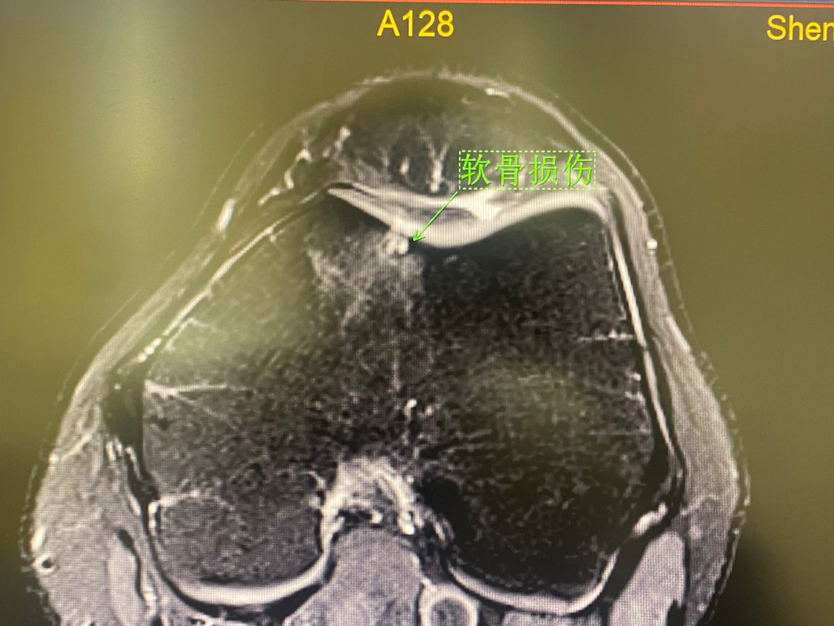

下面展示典型的膝关节软骨损伤,MRI核磁扫描可以清晰发现软骨损伤(3-4度),门诊检查非常常见!